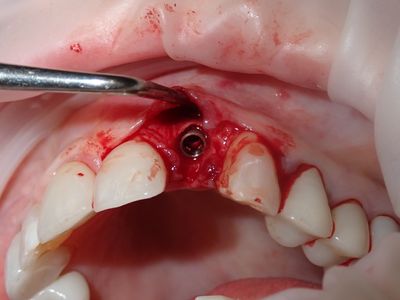

Atraumatic exo, loss of labial plate mid root about 2-3mm, CEJ and apical bone intact, region of thinner Labial-palatal bone, flapped site. osteotomy underprepared, implant placed with excellent stability. Buccal and socket grafted with 90/10 mix of mineralized cortical/xenograft followed by collagen membrane outside of socket on buccal, implant loaded with temporary crown out of centric and protrusive occlusion